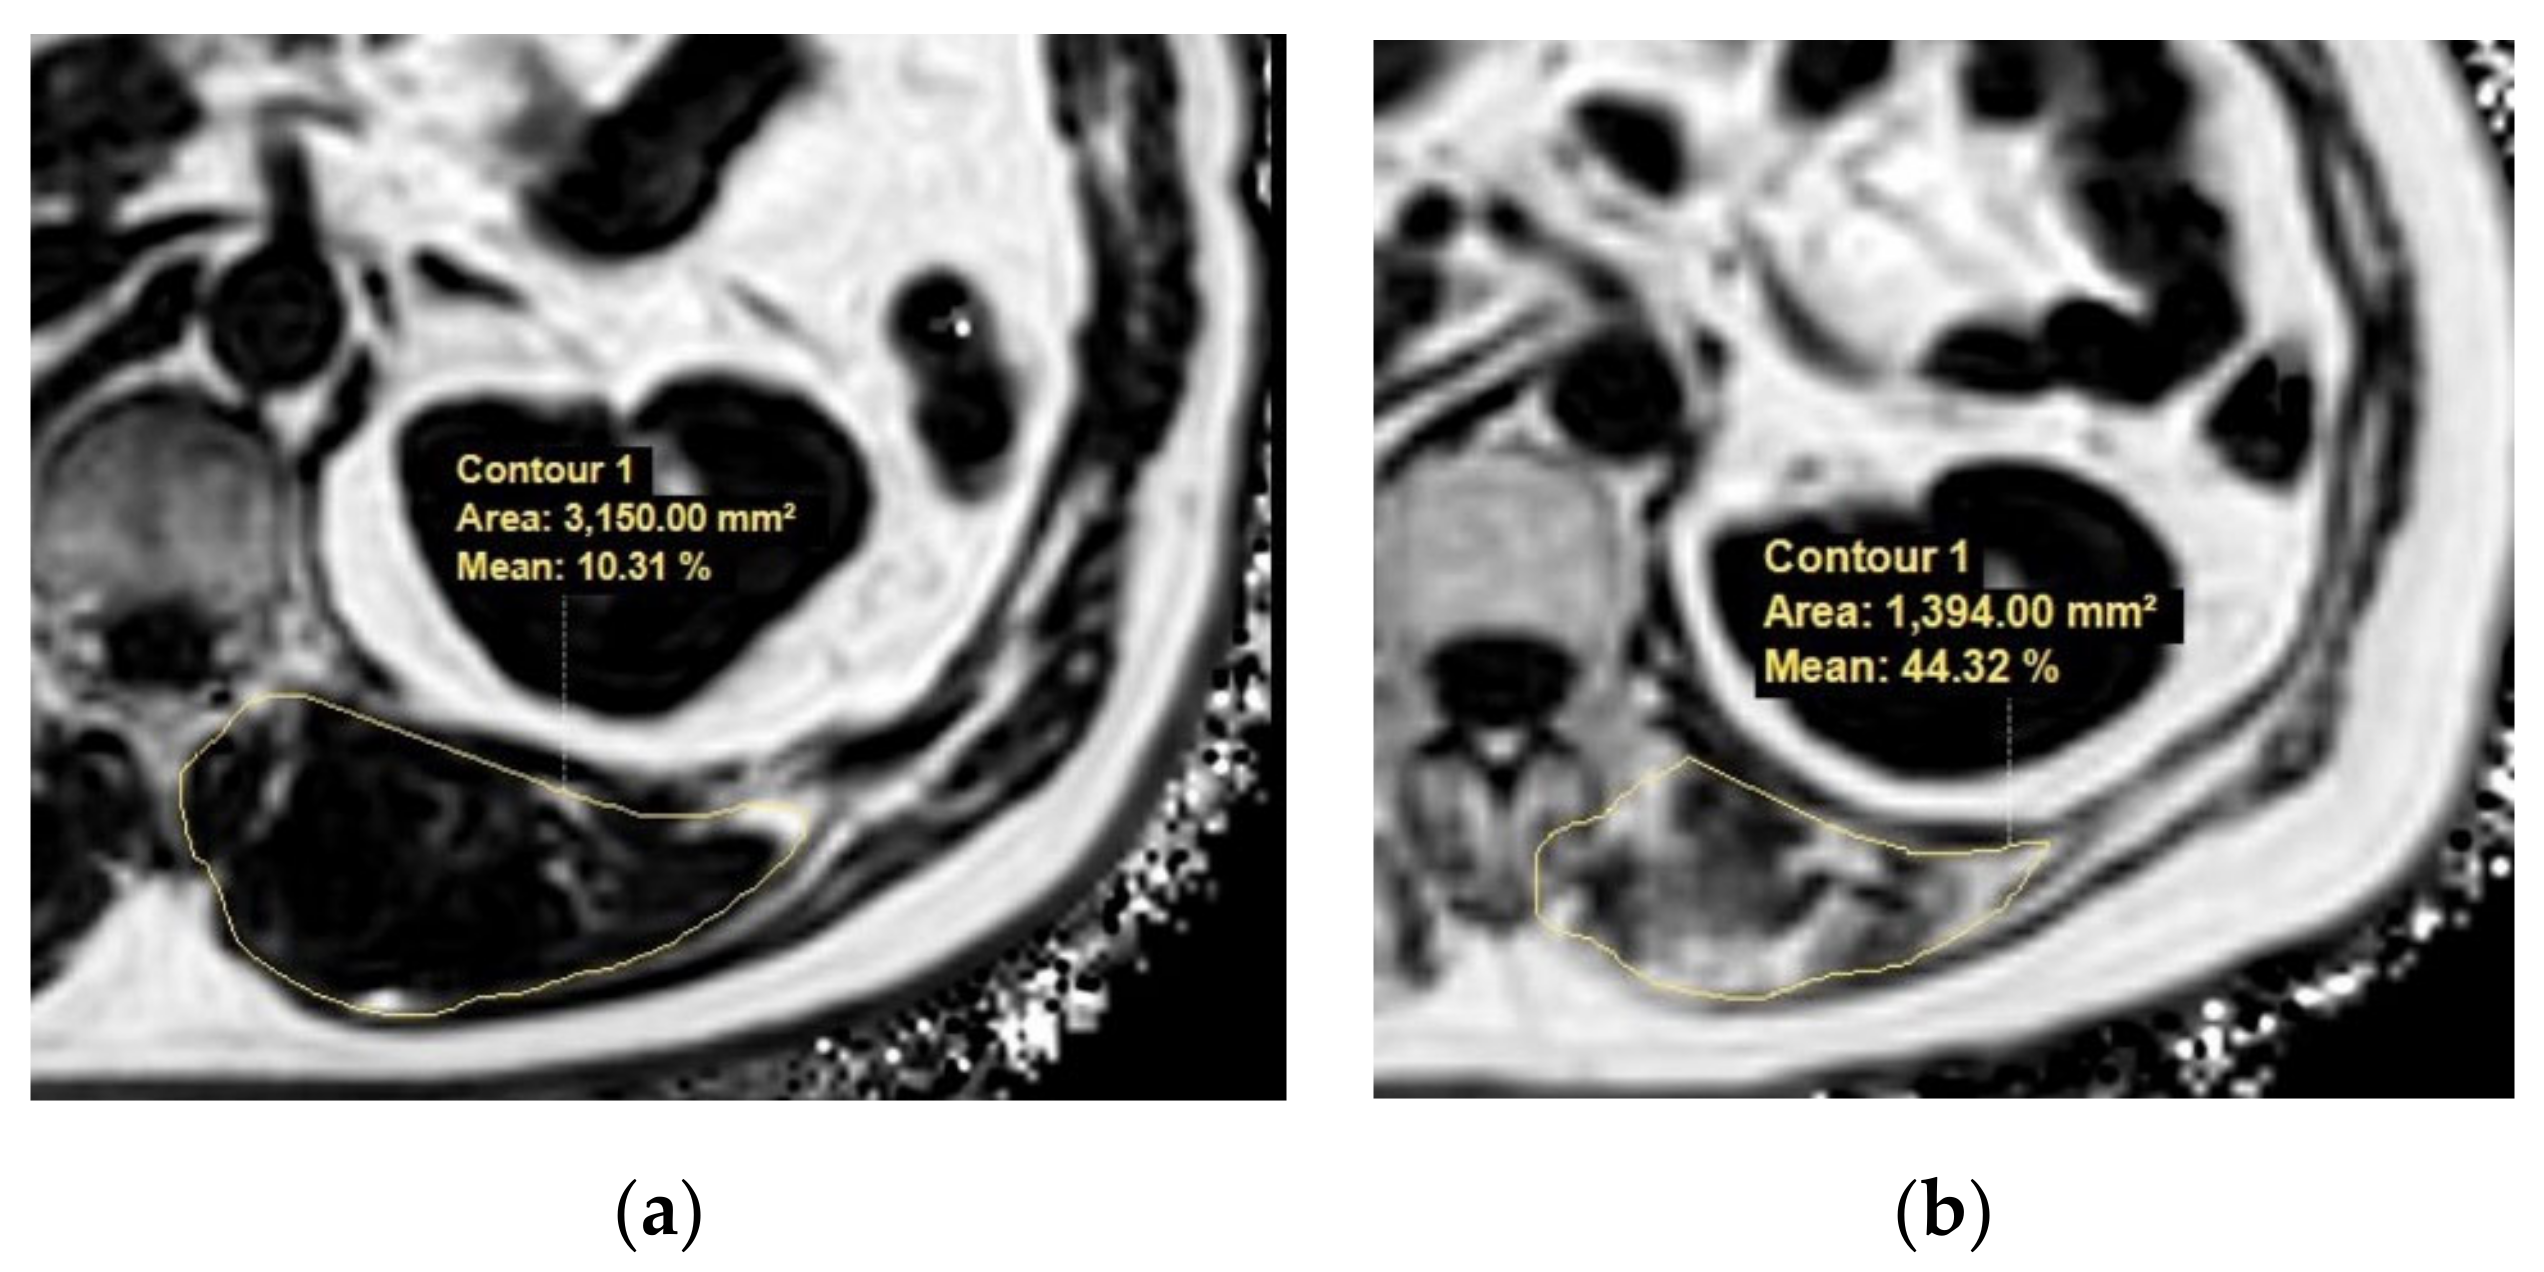

With advances in MRI techniques, the assessment of the chemical composition of tissue has also become possible. MR spectroscopy (MRS) is a representative MR technique that assesses the chemical composition of tissue [51,52]. DIXON-based MRI is a recent MRI technique challenging MRS by using a chemical shift to enable the selective reconstruction of fat signal- and water signal-only images [53,54]. Quantitative analysis using DIXON-based MRI showed an excellent correlation in MRS, which outperformed visual assessment in the detection of muscle fat content [55]. These fat quantification MRI techniques could be applied to the evaluation of sarcopenia in terms of muscle quality assessments in patients with chronic liver disease (Figure 4).

Figure 4.

Example MR images (fat fraction) of cross-section of the spinal muscles at the Superior Mesenteric Artery level in two patients with low fatty degeneration (a) and high fatty degeneration (b). (a) The area and fat fraction of the left spinal muscle were 3150 mm2 and 10.3%. (b) The area and fat fraction of the left spinal muscle were 1394 mm2 and 44.3%. An axial three-dimensional multi-echo-modified Dixon gradient echo sequence was used for the MRI. Imaging parameters for the sequence were as follows: six Echo Time (TE)s (first TE shortest automatic (0.9–1.2ms), delta TE 0.8–1.01ms); Repetition Time (TR) shortest automatic (5.8–6.3 ms); flip angle =3; field of view = 35 × 35 cm2; 3 mm slice thickness with no gap; matrix size = 300 × 300; number of slices = 60; scan time = 14.1 s; parallel imaging SENSE factor = 2; number of signal average = 1. The sequence automatically produces water, fat, fat fraction, R2*, and T2* maps.